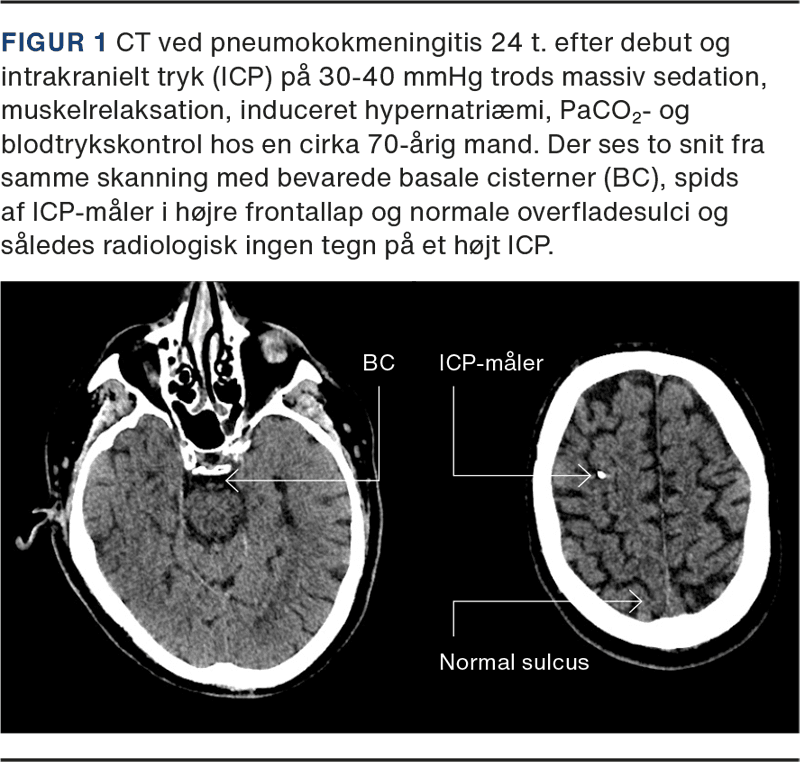

Rutinemæssig CT af cerebrum (CT-C) ved mistanke om ABM er ikke indiceret, da den ofte vil være normal [14, 22]. Derimod er CT-C indiceret ved nedsat bevidsthedsniveau, fokale neurologiske udfald, inklusive kranienervepåvirkning af enhver type, samt kramper [23]. Patienter med ABM visiteret til intensivafdelingen har en højere forekomst af patologisk CT-C med fund af diffust ødem, hydrocefalus og infarkter eller blødninger hos enkelte [1, 2, 16]. Dog er det væsentligt, at i det tidlige forløb af ABM kan ICP være svært forhøjet trods normal CT-C (Figur 1) [1, 6, 24].